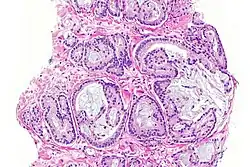

Gruczolakorak gruczołu krokowego, obraz mikroskopowy

W prawej górnej części preparatu obecny gruczolakorak, obok widoczne są prawidłowe gruczoły tworzące utkanie stercza

Gruczolakorak gruczołu krokowego, widoczna inwazja nerwu

W obrazie mikroskopowym gruczolakoraki gruczołu krokowego znacznie różnią się stopniem zróżnicowania (złośliwości histologicznej), dając spektrum nowotworów od dobrze zróżnicowanych (o niskiej złośliwości), które trudno odróżnić od prawidłowego utkania gruczołu krokowego do zmian o niskim zróżnicowaniu (o wysokiej złośliwości)[155]. Cechą wspólną dla wszystkich raków stercza jest obecność pojedynczej warstwy jednego typu komórek bez warstwy podstawnej, która jest widoczna w prawidłowych cewkach gruczołowych[156][152].

W dobrze zróżnicowanych nowotworach komórki nowotworowe tworzą stłoczone cewki gruczołowe o nieregularnym kształcie i różnej wielkości, które są wyścielone przez jedną warstwę komórek. Cewki gruczołowe są ułożone w dość bezładny sposób[156]. Kolejnym wzorem utkania typowym dla nacieku jest obecność atypowych struktur gruczołowych między dużymi, prawidłowymi gruczołami. Wraz z utratą różnicowania i tworzeniem struktur sitowatych, połączonych gruczołów lub słabo uformowanych gruczołów, coraz bardziej zaznacza się różnica między łagodnymi gruczołami a strukturami tworzonymi przez komórki nowotworowe[156]. Nisko zróżnicowane nowotwory są zbudowane z litych arkuszy lub sznurów komórek, a cewki gruczołowe są nieliczne lub poronne[156][157].